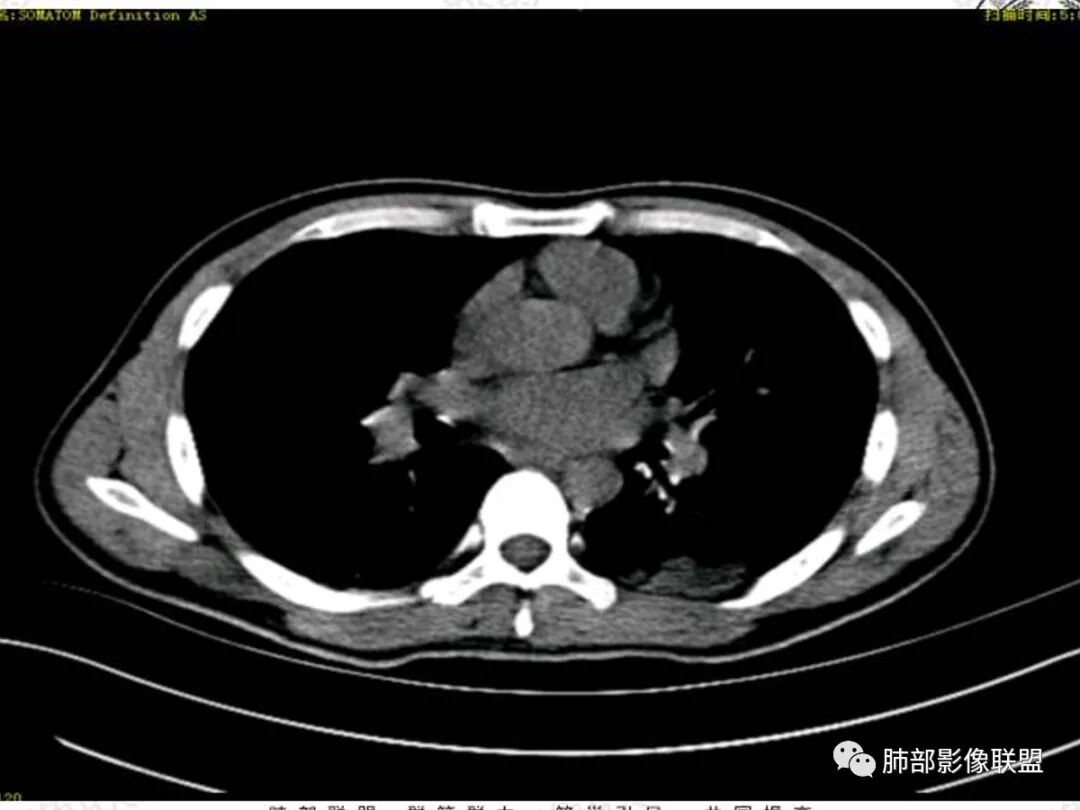

双肺叶透亮度对称性减低,呈磨砂状,小叶间隔规则增厚,上叶为甚,左右肺叶中轴间质增厚(示淋巴回流障碍),双肺叶弥散磨GGO征,以肺腺泡分布,双肺上,下叶融合片状,有重力分布特点,心脏大,肺动脉干增粗,首选心源性肺水肿,但无胸腔积液。与急性肺损伤和ARDS鉴别

青年男性,气促7小时入院,意识模糊,白细胞及中性粒明显增高,PCT增高,CRP不高,心率快,体温正常,血压正常。胸部CT:双肺上叶小叶间隔光滑增厚,中轴间质增厚,弥漫性磨玻璃、多发斑片影,以上肺、背侧分布为主。影像表现考虑为肺水肿。病因:病史不支持肾功能衰竭、心源性、高原性肺水肿,无发热,似乎也不支持细菌、病毒、真菌等感染引起。吸入毒物?吸入水?

肺水肿应该没啥疑问吧,就是病因的问题吧